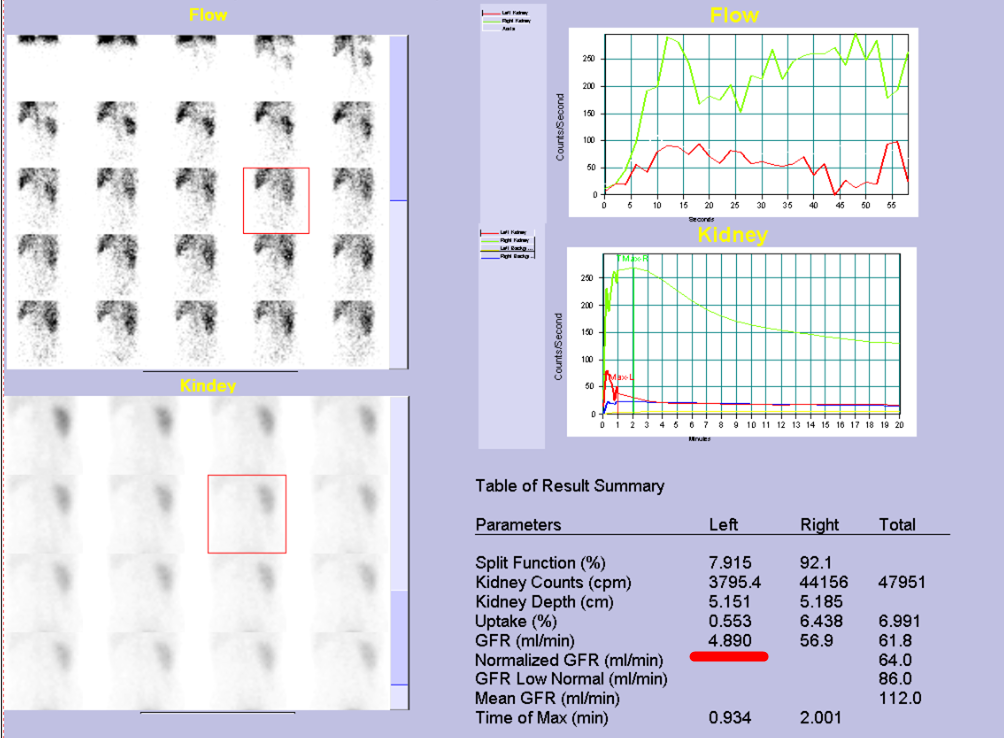

GFR:左侧仅4.89ml/min,与增强CT检查相符